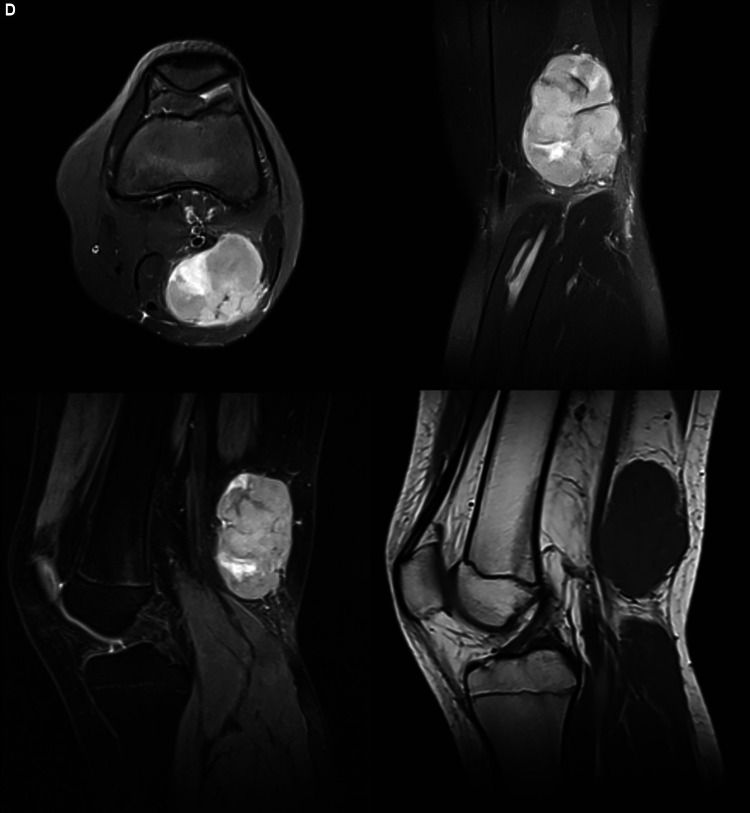

Abstract Image